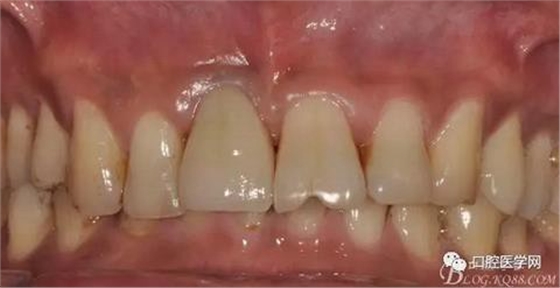

既 往 史:否認全身系統(tǒng)疾病史及藥物過敏史

圖4 術前正位頜面照